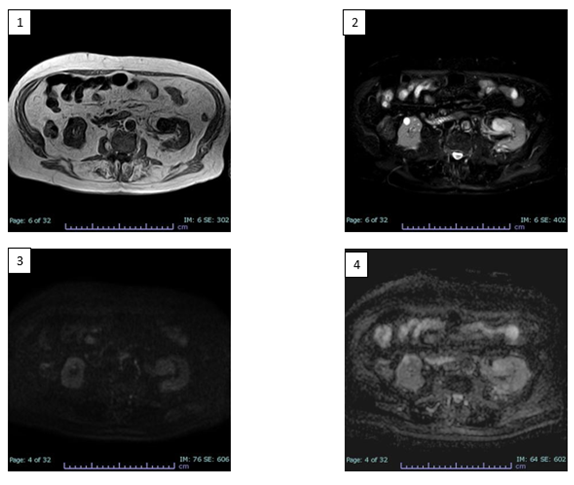

To better characterize the lesion, the patient underwent MRI examination of the upper and lower abdomen without and with intravenous CM (Figure 2).

MRI images showed T1-dependent signal hypointensity (Figure 2.1), inhomogeneous T2-dependent signal hyperintensity (Figure 2.3), and appears to have poor diffusion-weighted signal restriction (Figure 2.4, Figure 2.5). Overall, it is characterised by inhomogeneous contrast impregnation and has a greater axis of 32 x 23 x 26 mm (LL x AP x CC).

This technique confirms that the heteroformation did not generate compressive effects on the renal pelvis or vascular invasion. No significant mesenteric, para-aortic or retroperitoneal lymphadenopathy was evident.

Figure 2

Figure 2: RM scans before and after enhancing with CM. 1) Axial T1 TFE MRI sequence: heteroformation of the left renal sinus showing T1-dependent signal hypointensity. 2) Axial SPAIR T2 MRI sequence: inhomogeneous T2-dependent signal hyperintensity. 3) Axial DWI sB750 MRI sequence: poor diffusion-weighted signal restriction. 4) Axial ADC MRI sequence.

The imaging features reported in the case presentation show a tendency towards heterogeneity, indeed, both methods lean towards a pre-operative diagnosis of malignant lesions. At the CT scan without CM, an inhomogeneous hypointense lesion is evident in the left renal pelvis, at the level of the lower third, which shows uneven density in all its points, varying from punctiform areas with adipose-like densitometric coefficients (from -10 HU to -2 HU), to more frankly solid areas (49-20 HU) and to sections suggesting the presence of vascular components (37-60 HU). These findings are confirmed in subsequent scans enhanced with CM and, in particular, the lesion shows a frank enhancement in the more caudal peripheral portion in the arterial phase (up to 230 HU). In the subsequent portal phase a more homogeneous contrastographic filling of the entire lesion, with values of around 130 HU, was noted confirming the presence of an important hypervascular tissue component. However, the lesion shows no frank signs of invasiveness or compression of the surrounding structures, in the absence of dilation upstream and downstream of the lesion. Furthermore, there are no signs of necrosis or calcifications within the lesion. MRI images also show characteristics of inhomogeneous signal intensity, reflecting its vascular nature, revealing signal hypointensity in T1 sequences, inhomogeneous signal hyperintensity in T2 and poor signal restriction in DWI, indicative of poor cellularity. In line with the literature, our experience confirms the complexity of discriminating against the dyskaryokinetic nature of such a complex lesion with CT investigations, even if supplemented by MRI acquisitions. Thus, even if there are many overlapping features among the entities placed in benign vs. malignant differential diagnosis from the anatomopathological perspective, this diagnostic difficulty appears even more evident to the radiologist's eye. Indeed, it is not surprising that AH is still treated with demolitive approaches, such as total or partial nephrectomy, or more rarely local excision, with the aim of clarifying the nature of the lesion. However, in support of the biologically indolent nature of AH, some limited evidence exists on a small group of patients brought to follow-up which showed no tendency for recurrence or metastasis [3,9].